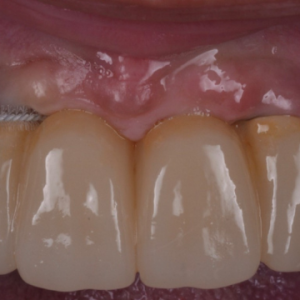

La estabilidad del hueso marginal y del tejido blando alrededor de los implantes dentales se ha establecido como la principal característica para asegurar la salud del implante.La condición...

La integración del tejido blando periimplantario sigue siendo fundamental para el éxito a largo plazo de la terapia con implantes. La formación de una barrera temprana y duradera para proteger las...